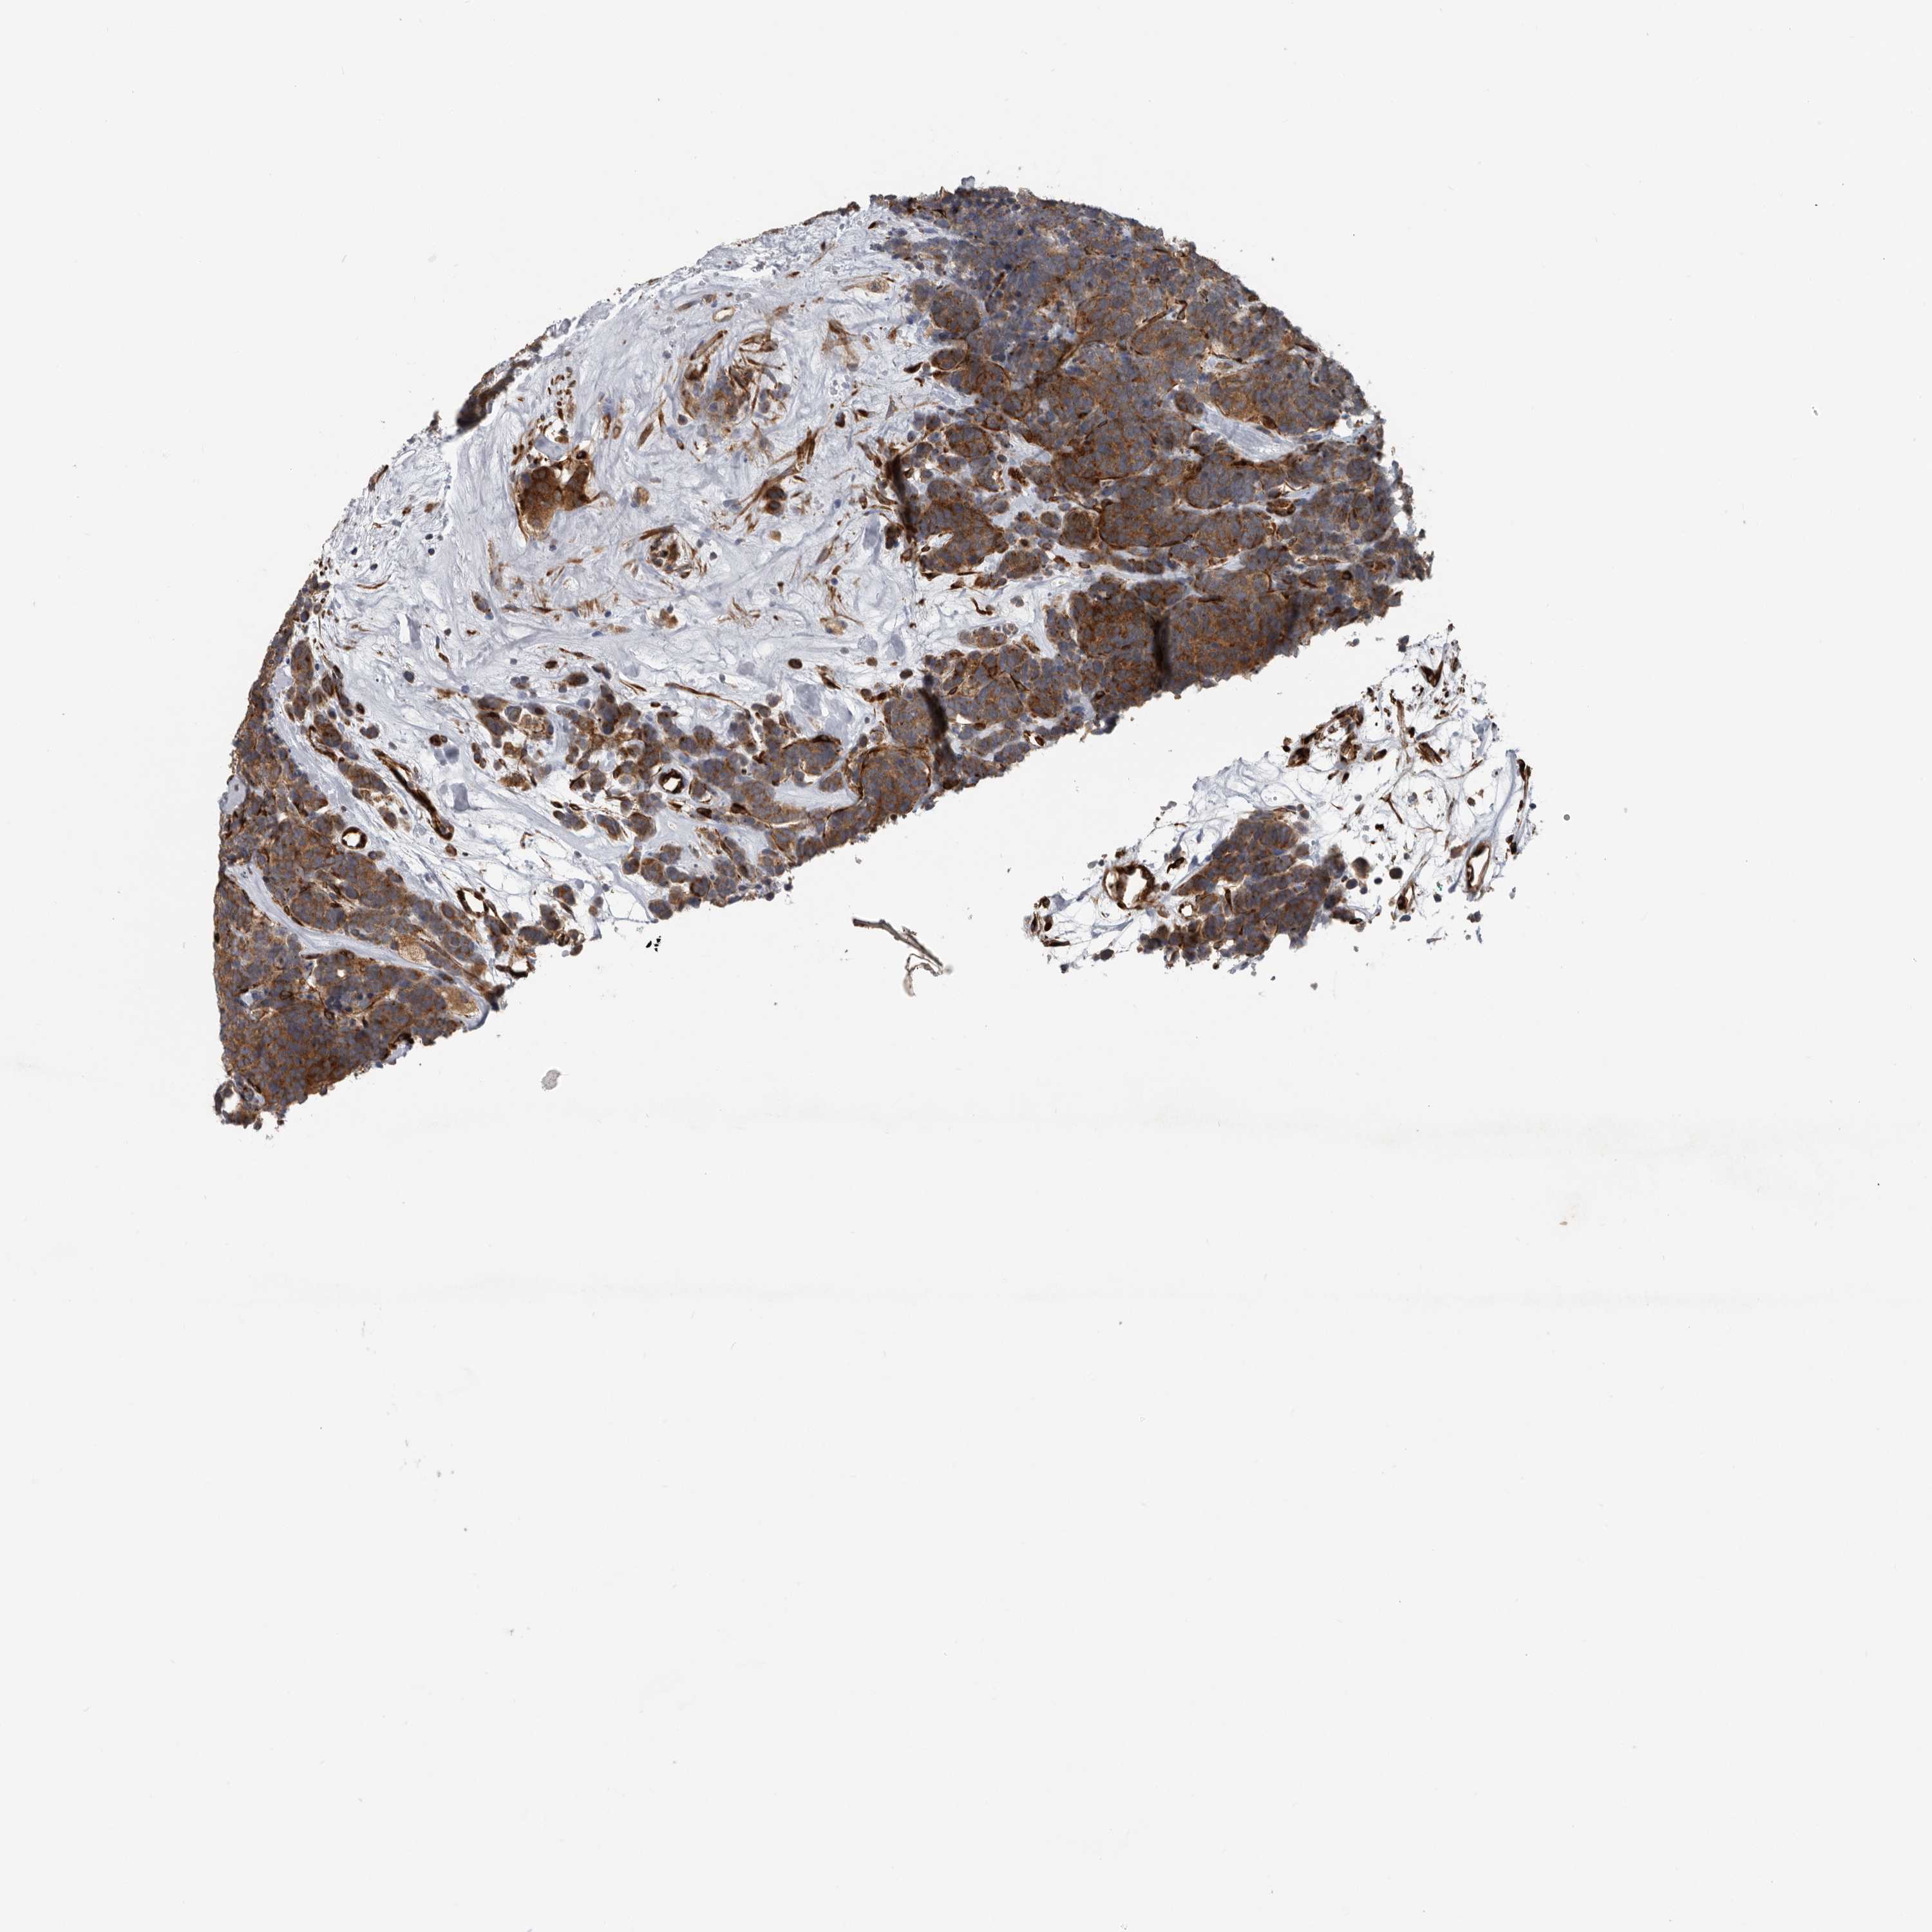

CANCER CARCINOID Show tissue menu

CARCINOID - Protein expressioni

A mouse-over function shows sample information and annotation data. Click on an image to view it in a full screen mode. Samples can be filtered based on level of antibody staining by selecting one or several of the following categories: high, medium, low and not detected. The assay and annotation is described here.

Each image is clickable and will lead to virtual microscopy that enables deeper exploration of all samples and also displays staining intensity scores, fraction scores and subcellular localization as well as patient and tissue information for each sample.

Antibody HPA028355

Antibody HPA028357

Staining

High

Medium

Low

Not detected

Intensity

Strong

Moderate

Weak

Negative

Quantity

>75%

75%-25%

<25%

None

Location

Nuclear

Cytoplasmic/membranous

Cytoplasmic/membranous,nuclear

Carcinoid, malignant, NOS